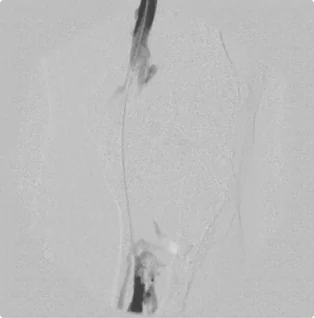

Female – Age 91

Referred by her Podiatrist for Gangrene, Non-Healing Wounds on her Toes and Absent Pulse In the Foot

Her podiatrist referred this patient for an emergency evaluation of her left foot. The foot was progressively darkening (turning black due to lack of blood flow), had no detectable pulse, and had two non-healing wounds on the toes. Due to her absent arterial flow through the leg, the foot was no longer receiving any oxygen and was quickly dying; she was at critical risk for amputation. Following her ultrasound, she was immediately scheduled for intervention. Dr. Goldstein treated her arteries with thorough atherectomy, stenting, and angioplasty all the way down into her foot to create a clear arterial blood flow through the limb. With restored blood flow, the color in her foot slowly returned to normal, her pulse returned, and her wounds began to heal.

Before treatment (left), she had no arteries flowing down into the foot, causing the slow death of the foot. After extensive treatment (right), she had two strong arteries flowing into the foot, and she began to recover.